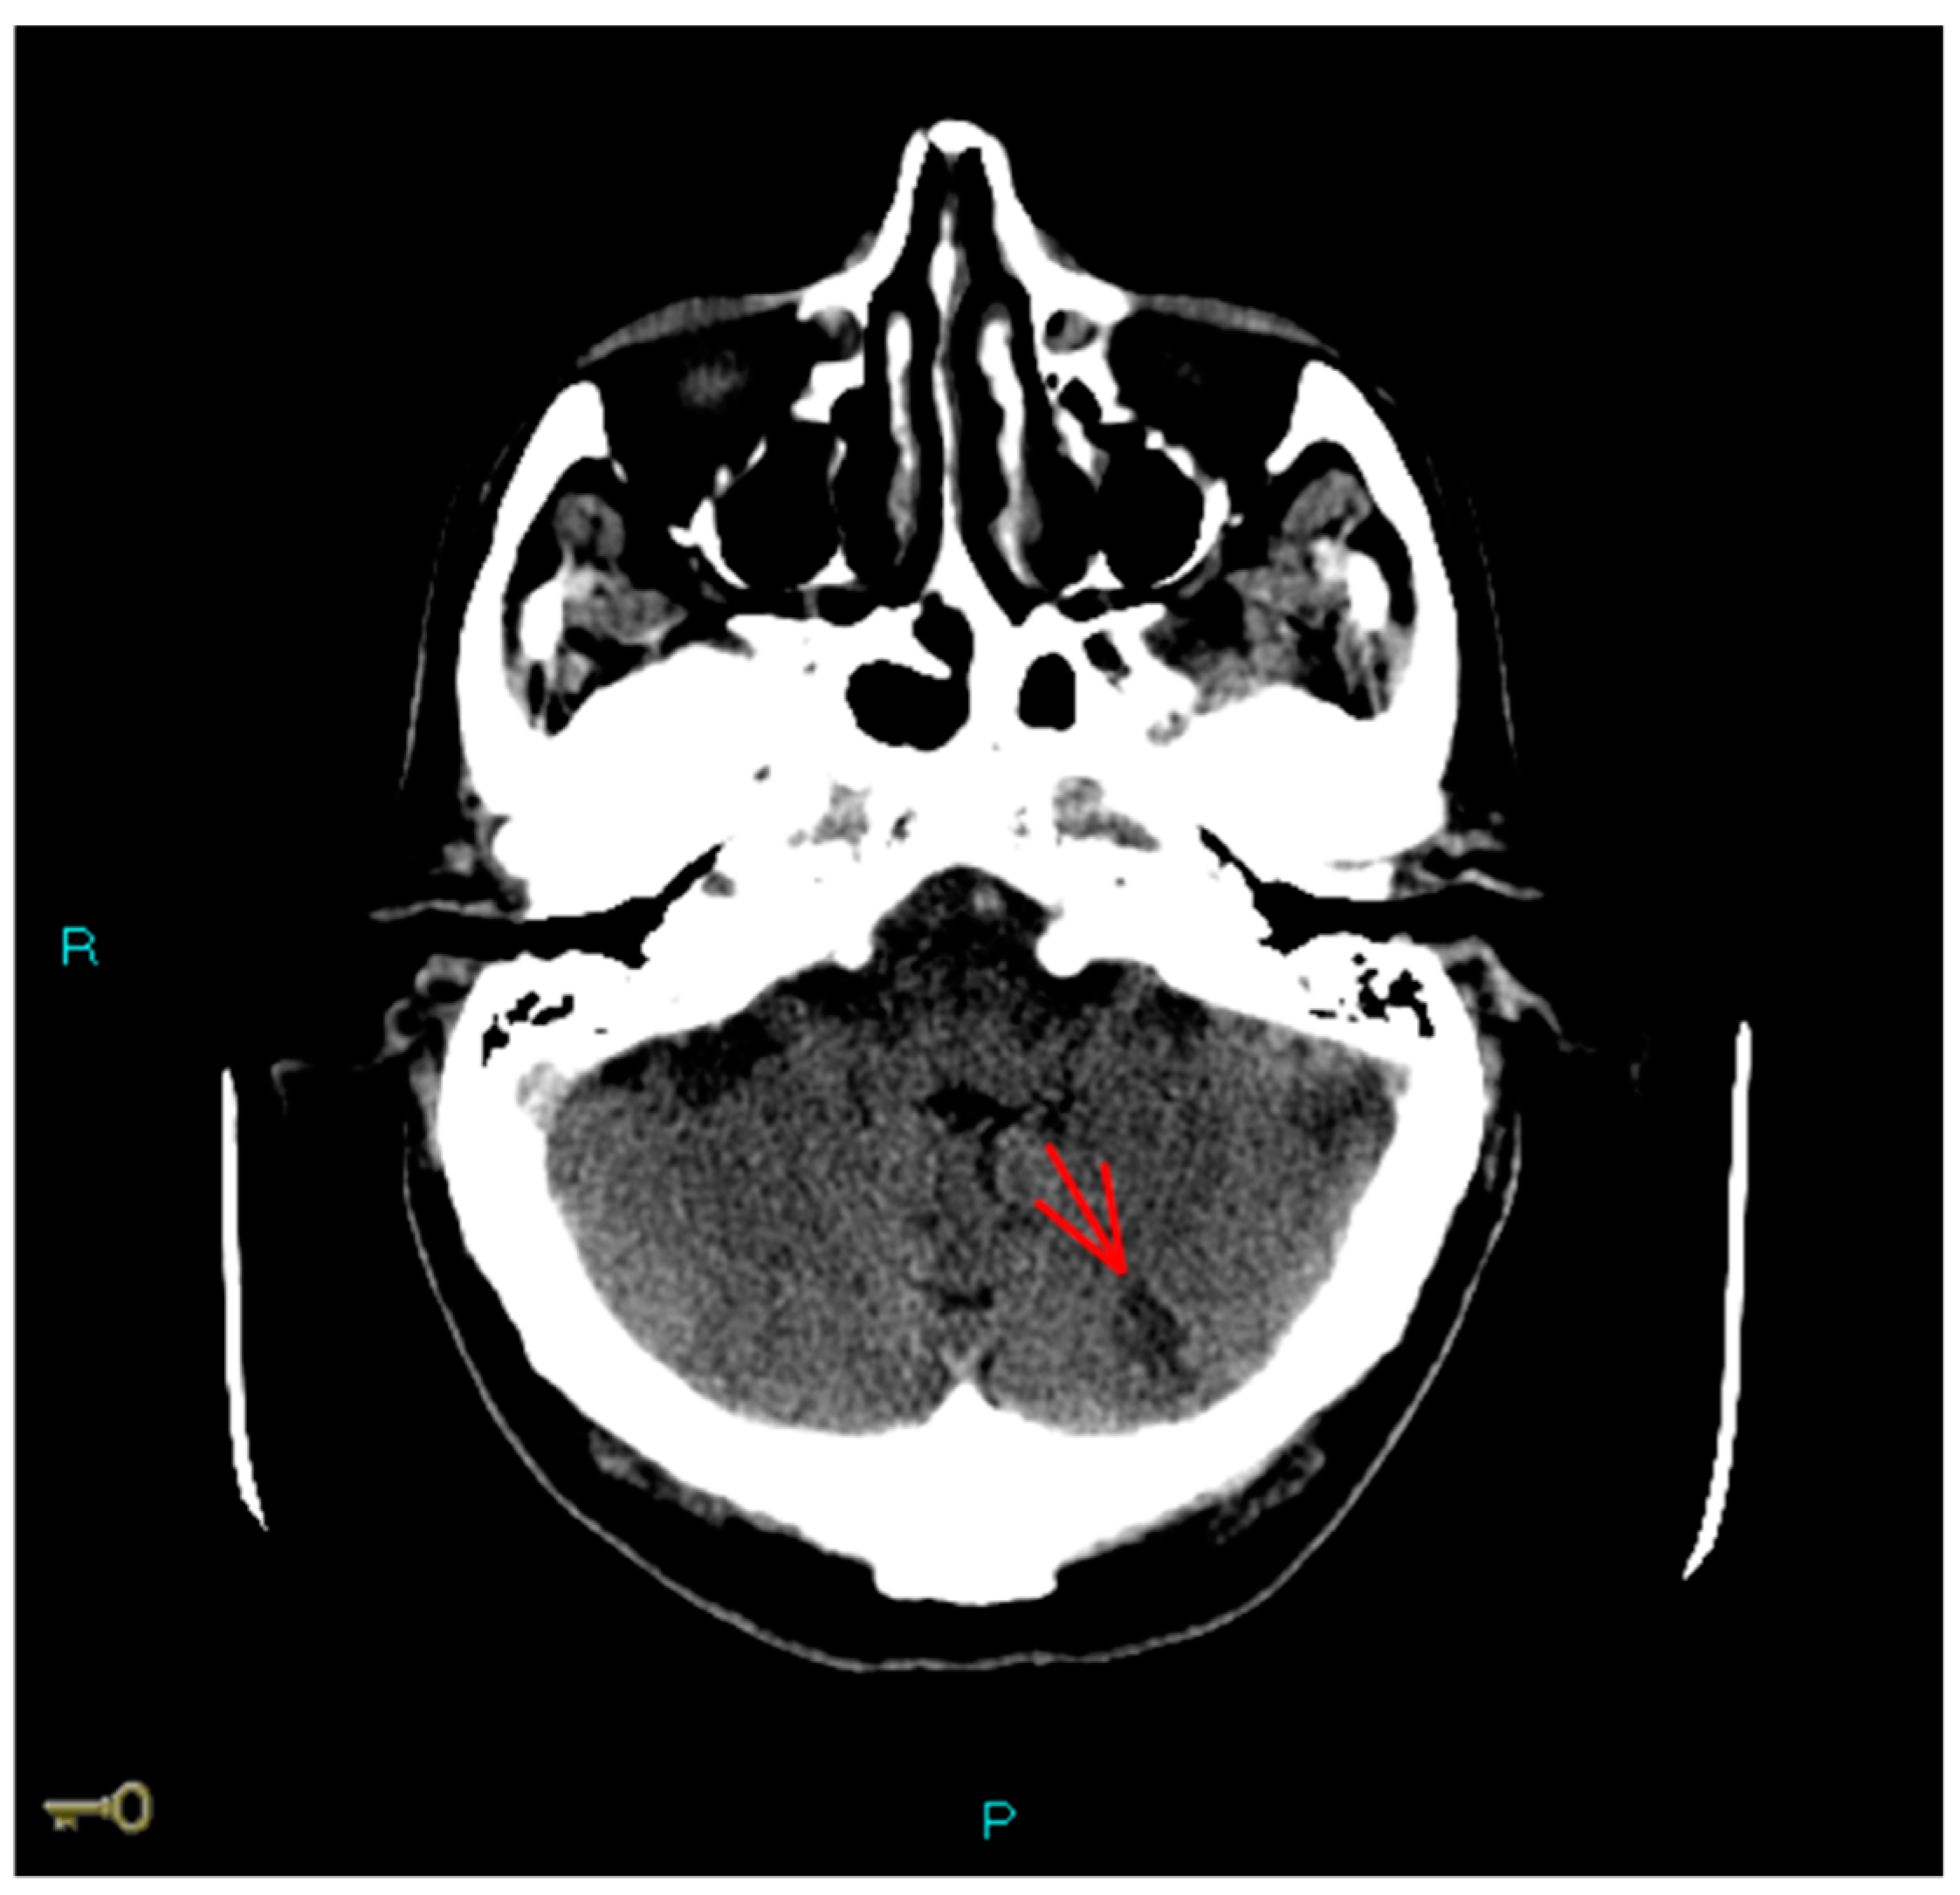

1. Case Report

2. Case Discussion

2.3. Iatrogenic Interatrial Septal Defect, In Situ Thrombosis and Paradoxical Embolism